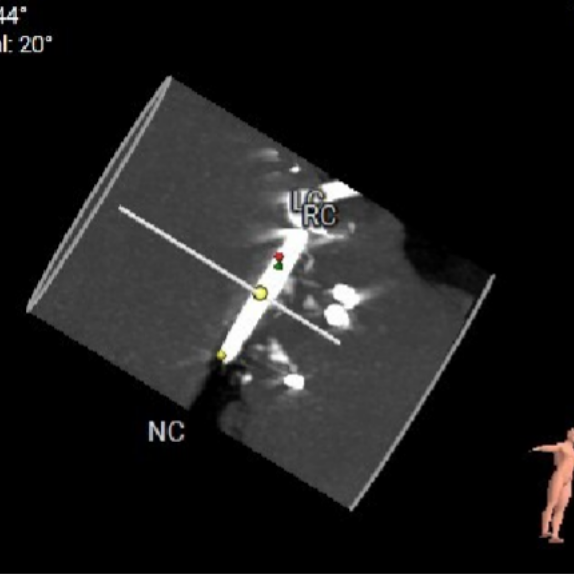

术中造影角度:右窦中心位 LAO 27°,CRA 9°。

右窦中心

释放角度